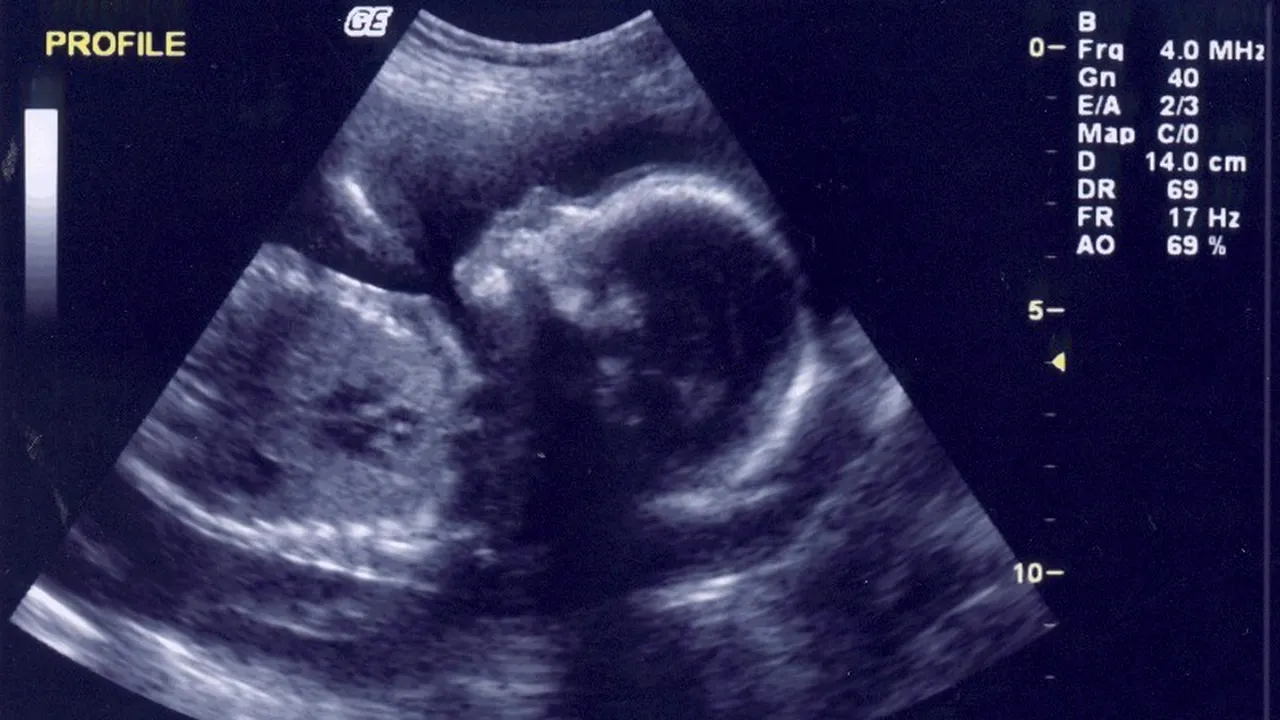

Un bebeluș născut la sfârșitul săptămânii trecute la spitalul din Petroșani nu are picioare de la genunchi și jos și nici brațul drept, iar părinții îi acuză pe cei doi medici care au supravegheat sarcina că nu au descoperit malformațiile, deși mama a făcut ecografii, fiind asigurată că este bine.

Bebelușul s-a născut, duminica trecută, la Spitalul de Urgență din Petroșani, cu mai mai multe malformații, respectiv lipsa picioarelor de la genunchi în jos și lipsa brațului drept de la cot în jos, iar părinții îi acuză pe cei doi medici care au supravegheat sarcina că nu au descoperit malformațiile, deși mama a făcut ecografii, fiind asigurată că este bine.

Mama copilului, Elena Oprea, în vârstă de 32 de ani, spunea că vinerea trecută, cu două zile înainte de naștere, i-a fost făcută ultima ecografie, la o clinică privată din oraș, de către medicul Cristina Mustocea, care a asigurat-o că bebelușul nu are nicio problemă și că se va naște la începutul lunii septembrie.

El afirma că medicul care a făcut ecografiile în cabinetul privat, Cristina Mustocea, i-a spus, la una dintre investigații, care a avut loc la 23 de săptămâni de sarcină, că îi vede talpa și un călcâi: „Mi-a arătat talpa, mi-a arătat călcâiul. Unde au dispărut? Credeam că voi duce acasă un băiat întreg și am ajuns să fim întreaga familie în stare de șoc. I-am cumpărat papucei. Unde mai pun eu acești papucei?”.

Bărbatul a explicat că pe toată durata sarcinii soția sa a fost supravegheată de doctorița Cristina Mustocea de la Spitalul de Urgență din Petroșani, care i-a făcut mamei trei ecografii în cabinetul său privat, plătind de fiecare dată pentru investigații și fiind asigurați că sarcina este în evoluție, iar copilul se dezvoltă normal. De asemenea, mama a fost supravegheată în timpul sarcinii și de doctorița Sidonia Fabiș, de la același spital, și la care a ajuns inițial femeia, în luna ianuarie, când a aflat că este însărcinată.

La prima vizită la spital, femeia a fost trimisă de către medicul Sidonia Fabiș să facă ecografii într-un cabinet privat, spunându-i-se că aparatul din spital este vechi. Ulterior, femeia a ajuns la Cristina Mustocea pentru ecografii, aceste investigații fiind văzute, însă, și de Sidonia Fabiș, care, de asemenea, i-a asigurat pe părinți că bebelușul nu are nicio problemă.

Întrebată dacă a observat problema la prima ecografie, făcută în luna ianuarie, Fabiș a spus că fătul era prea mic pentru a putea observa o problemă.

„Era prea mic la șase-șapte săptămâni, ce să vezi? Sacul gestațional și acea mică ființă care se va forma, se vede cordul și atât. La șase-șapte săptămâni nimic altceva”, a spus medicul.